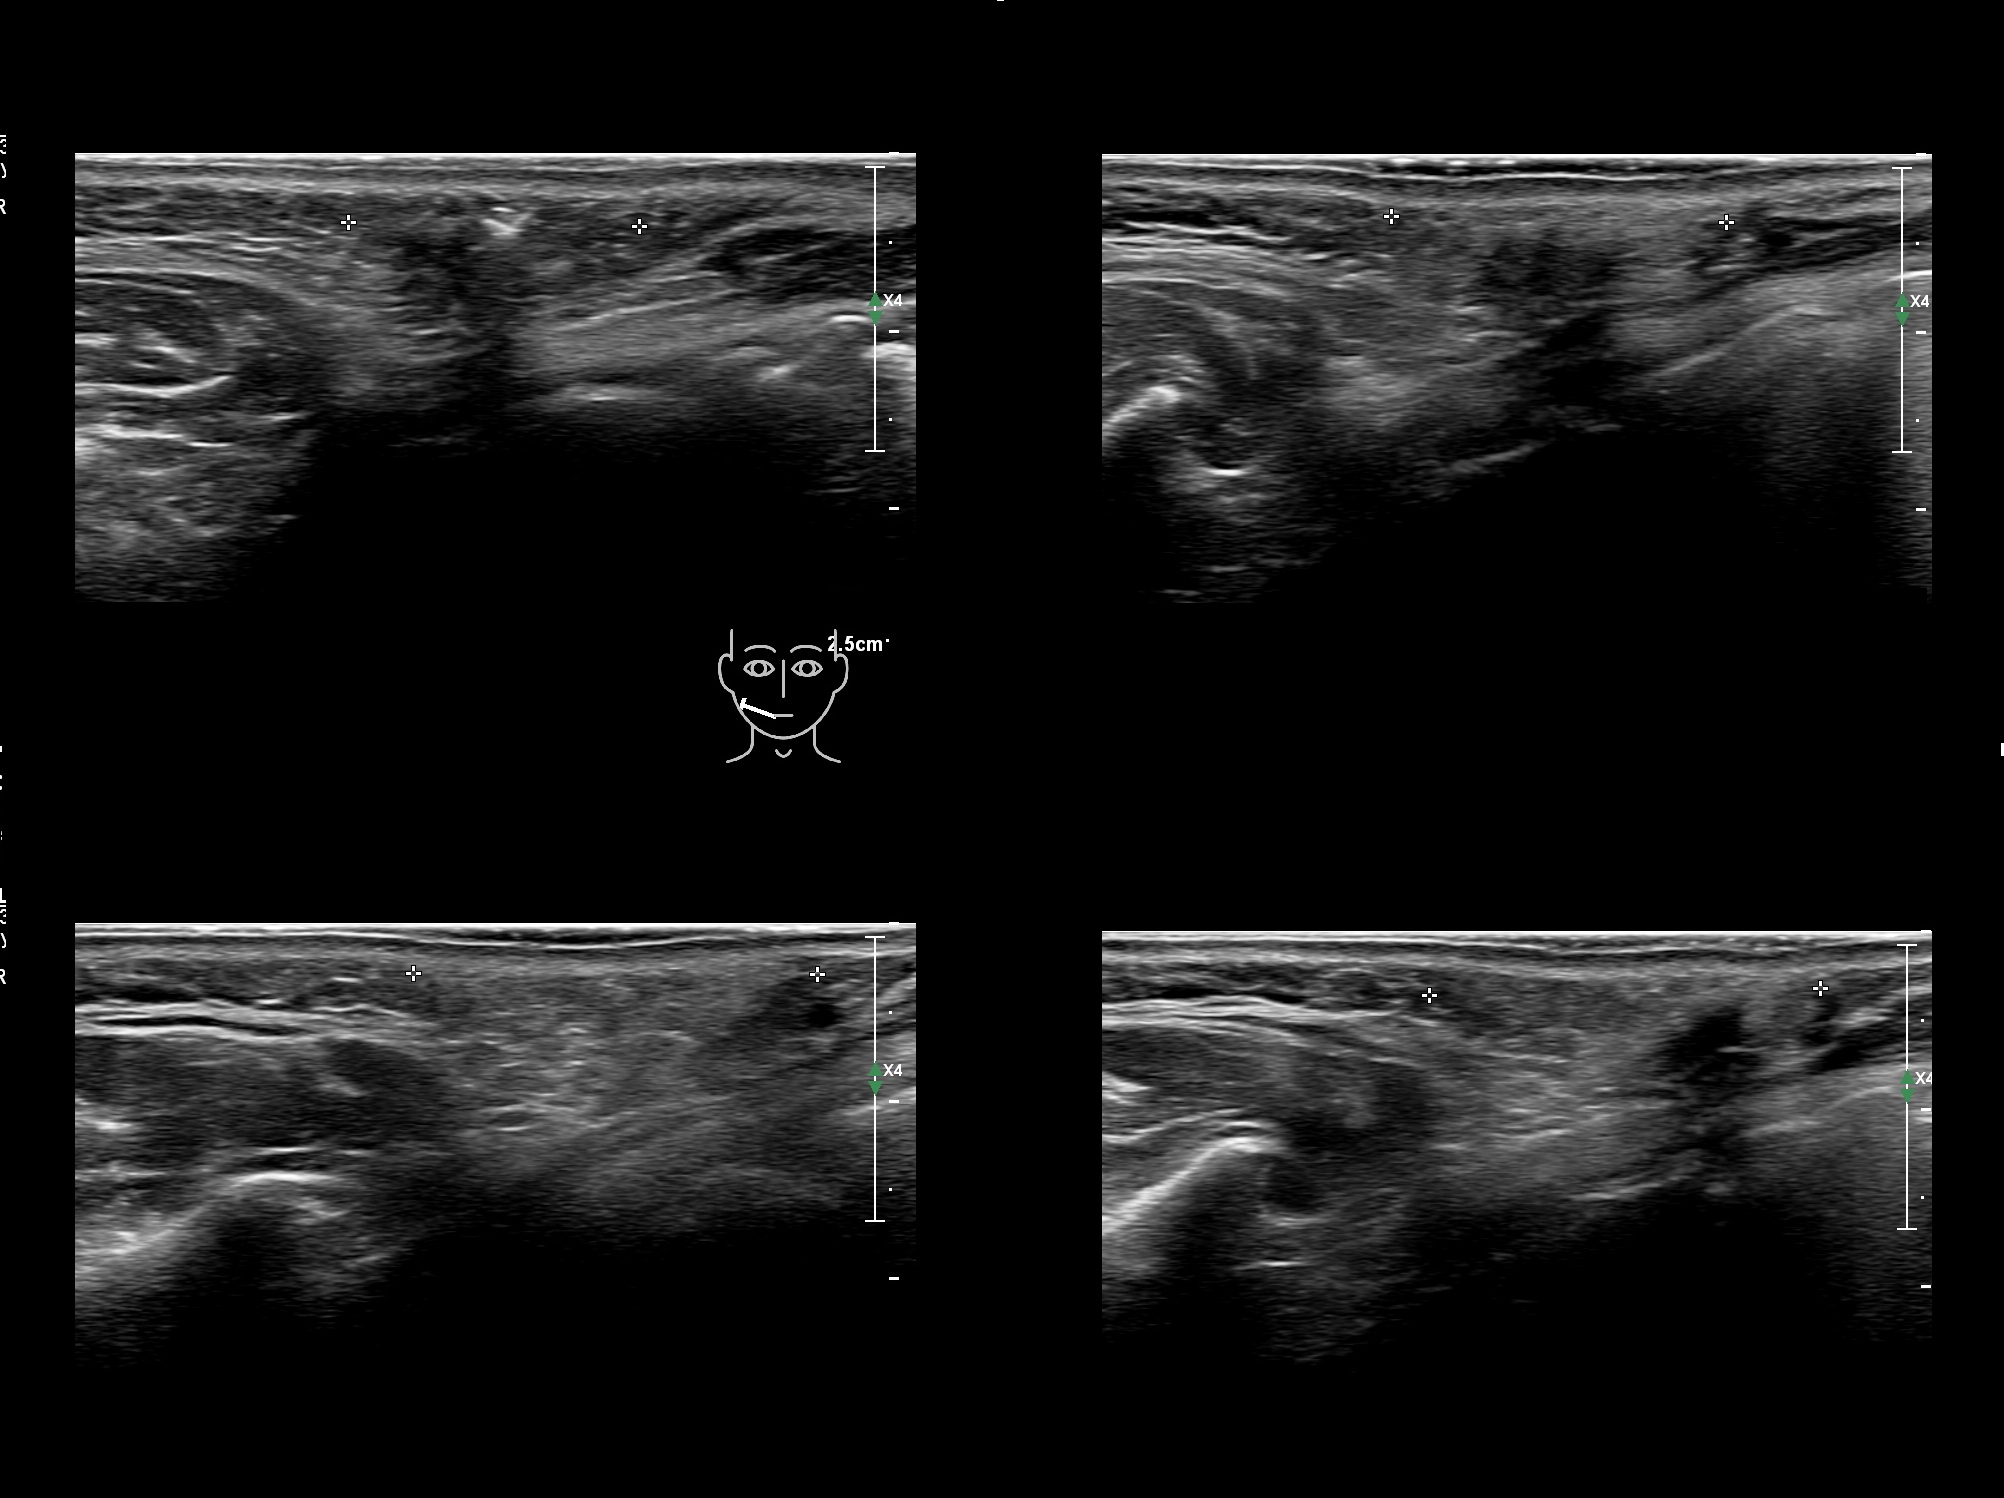

Fillers

Draw in the second image below where the fillers are located. To check if your answer is correct, swipe the first image to the right.